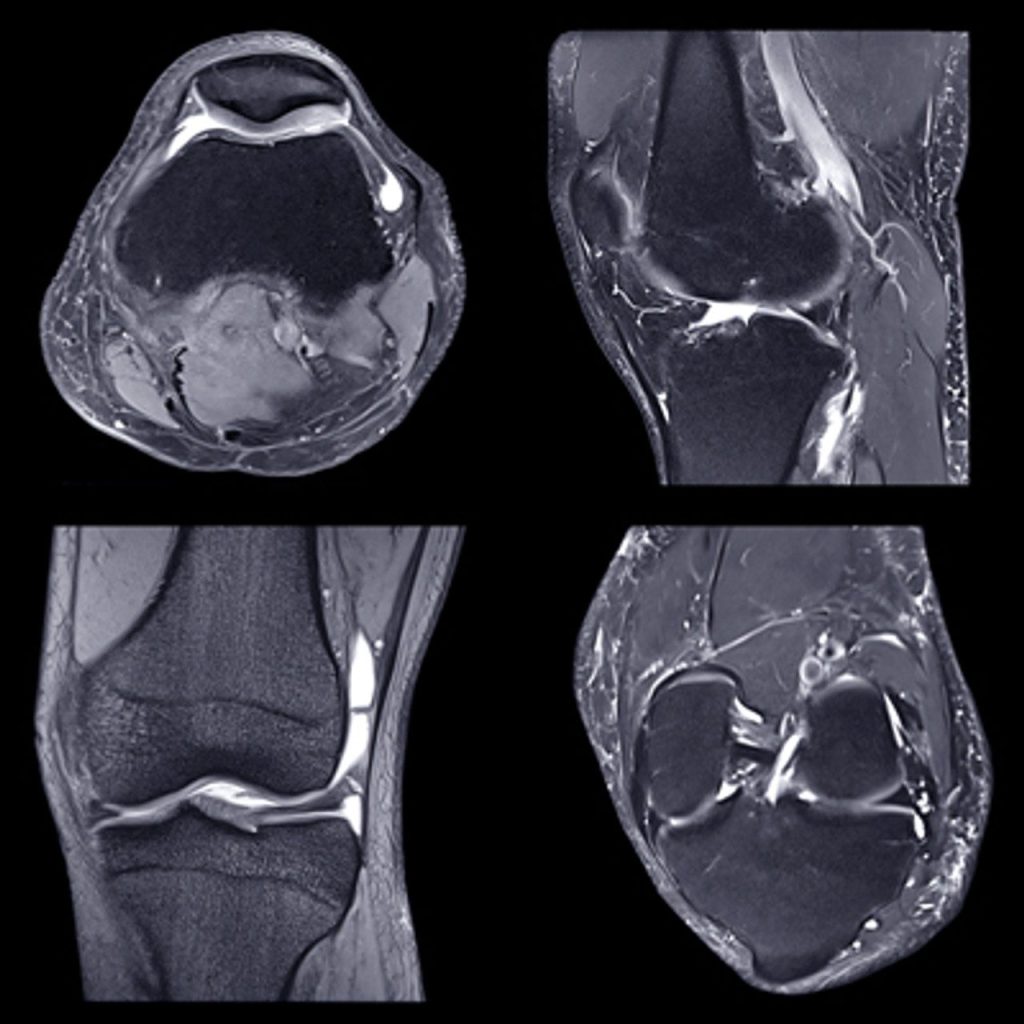

- Patterns of Knee Injury — Donald Resnick, MD

- Anterior Knee Pain and Patellofemoral Maltracking — Mini Pathria, MD

- MRI of the Knee – How Important are the Corners? — Lawrence M. White MD, FRCPC

- Menisci and Cruciates – Is There Anything New I Need to Know? — Christine B. Chung, MD

- Imaging of Cartilage and Cartilage Repair – What Does My Surgeon Need to Know? — Richard Kijowski, MD

- Scroll with the Experts – Knee — Christine B. Chung, MD